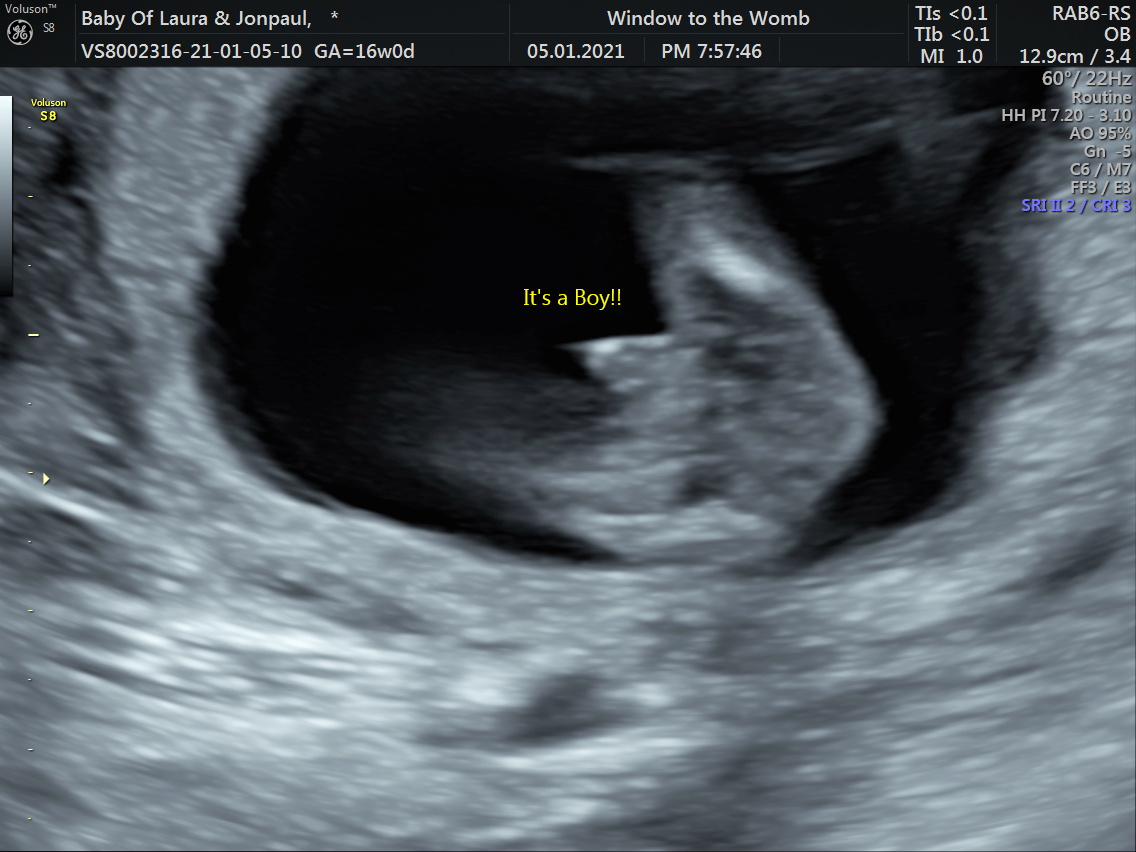

Scratch that I had a gender scan today just over 15 weeks it’s a boy I’m completely crushed. Didn’t think I would feel this bad. How long after having a baby can I sway?

How sure were they? Usually they don't give confirmation till 18+.

Attachment 43098Attachment 43099

These were from a video I got not sure if that is the penis at the end

Attachment 43110Attachment 43111Attachment 43112

Got the potty shots